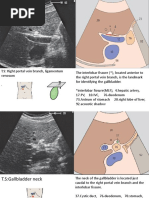

1. Right upper quadrant ( peri-hepatic) view:

INTERCOSTAL TECHNIQUE

SUBCOSTAL TECHNIQUE

Commonly used

Probe in right infracostal margin lateral to

Probe in midaxillary line between 8-11 rib midclavicular line

Probe indicator towards pt posterior axilla Deep breath pushes subcostal structures into view

(pt co-operation needed)

Rotate counterclockwise to reduce rib

shadowing Colonic gas in hepatic flexure-limits visualisation

NEGATIVE RUQ SCAN POSITIVE RUQ SCAN

Free

floating tip

Liver

of liver

Diaphragm

Kidney

31

2. LEFT UPPER QUADRANT (PERISPLENIC WINDOW)

Intercostal approach-between ribs 9 and 10 or

10 and 11 in posterior axillary line – indicator to

pt’s head

NEGATIVE LUQ SCAN POSITIVE LUQ SCAN